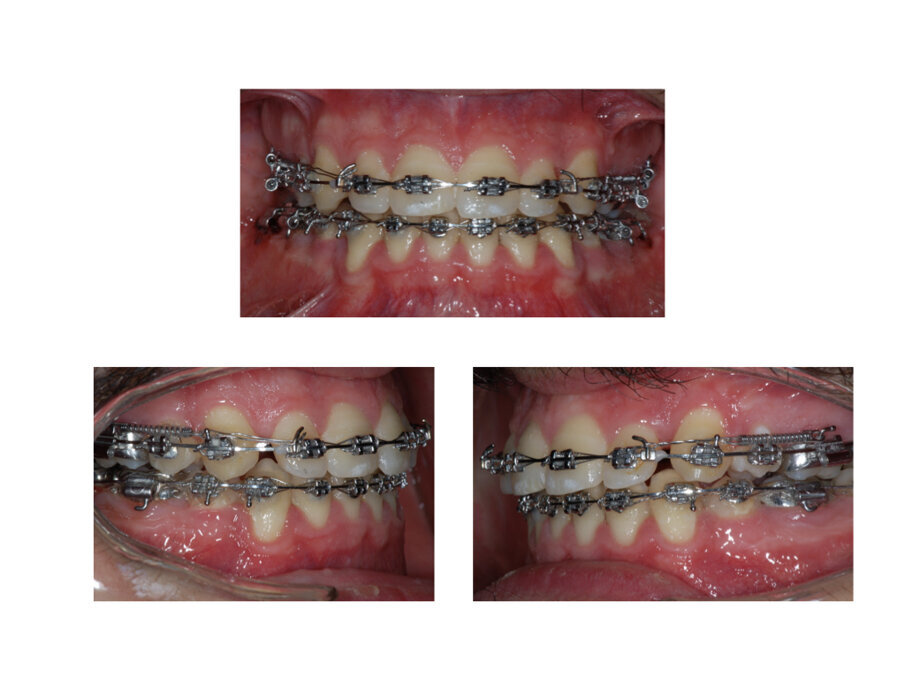

Valutazione Intraorale

Il paziente presenta tutti gli elementi dentali permanenti erotti, vi è l’agenesia del 4.8 ed 1.8 e l’inclusione del 3.8 e 2.8 (Fig. 1). L’igiene orale è media ed il biotipo gengivale è spesso. L’arco mascellare ha una forma ad “U”, è asimmetrica per eruzione palatina del 1.5 con chiusura dello spazio in arcata dell’elemento dentale. A seguito della migrazione mesiale dentale dell’1.6, quest’ultimo si presenta mesioruotato assialmente. Si ha un affollamento di 4 mm, la curva di Spee è di 1,5 mm. La relazione inter-arcata mostra una classe I molare bilaterale, una classe III canina destra, una classe II canina sinistra. L’OJ è ridotto <2 mm e l’OB è <2 mm. Dato l’affollamento asimmetrico presente vi è un evidente alterazione della linea mediana incisale. Vi è una leggere discrepanza trasversale della mandibola con una tendenza occlusale di testa a testa sinistra.